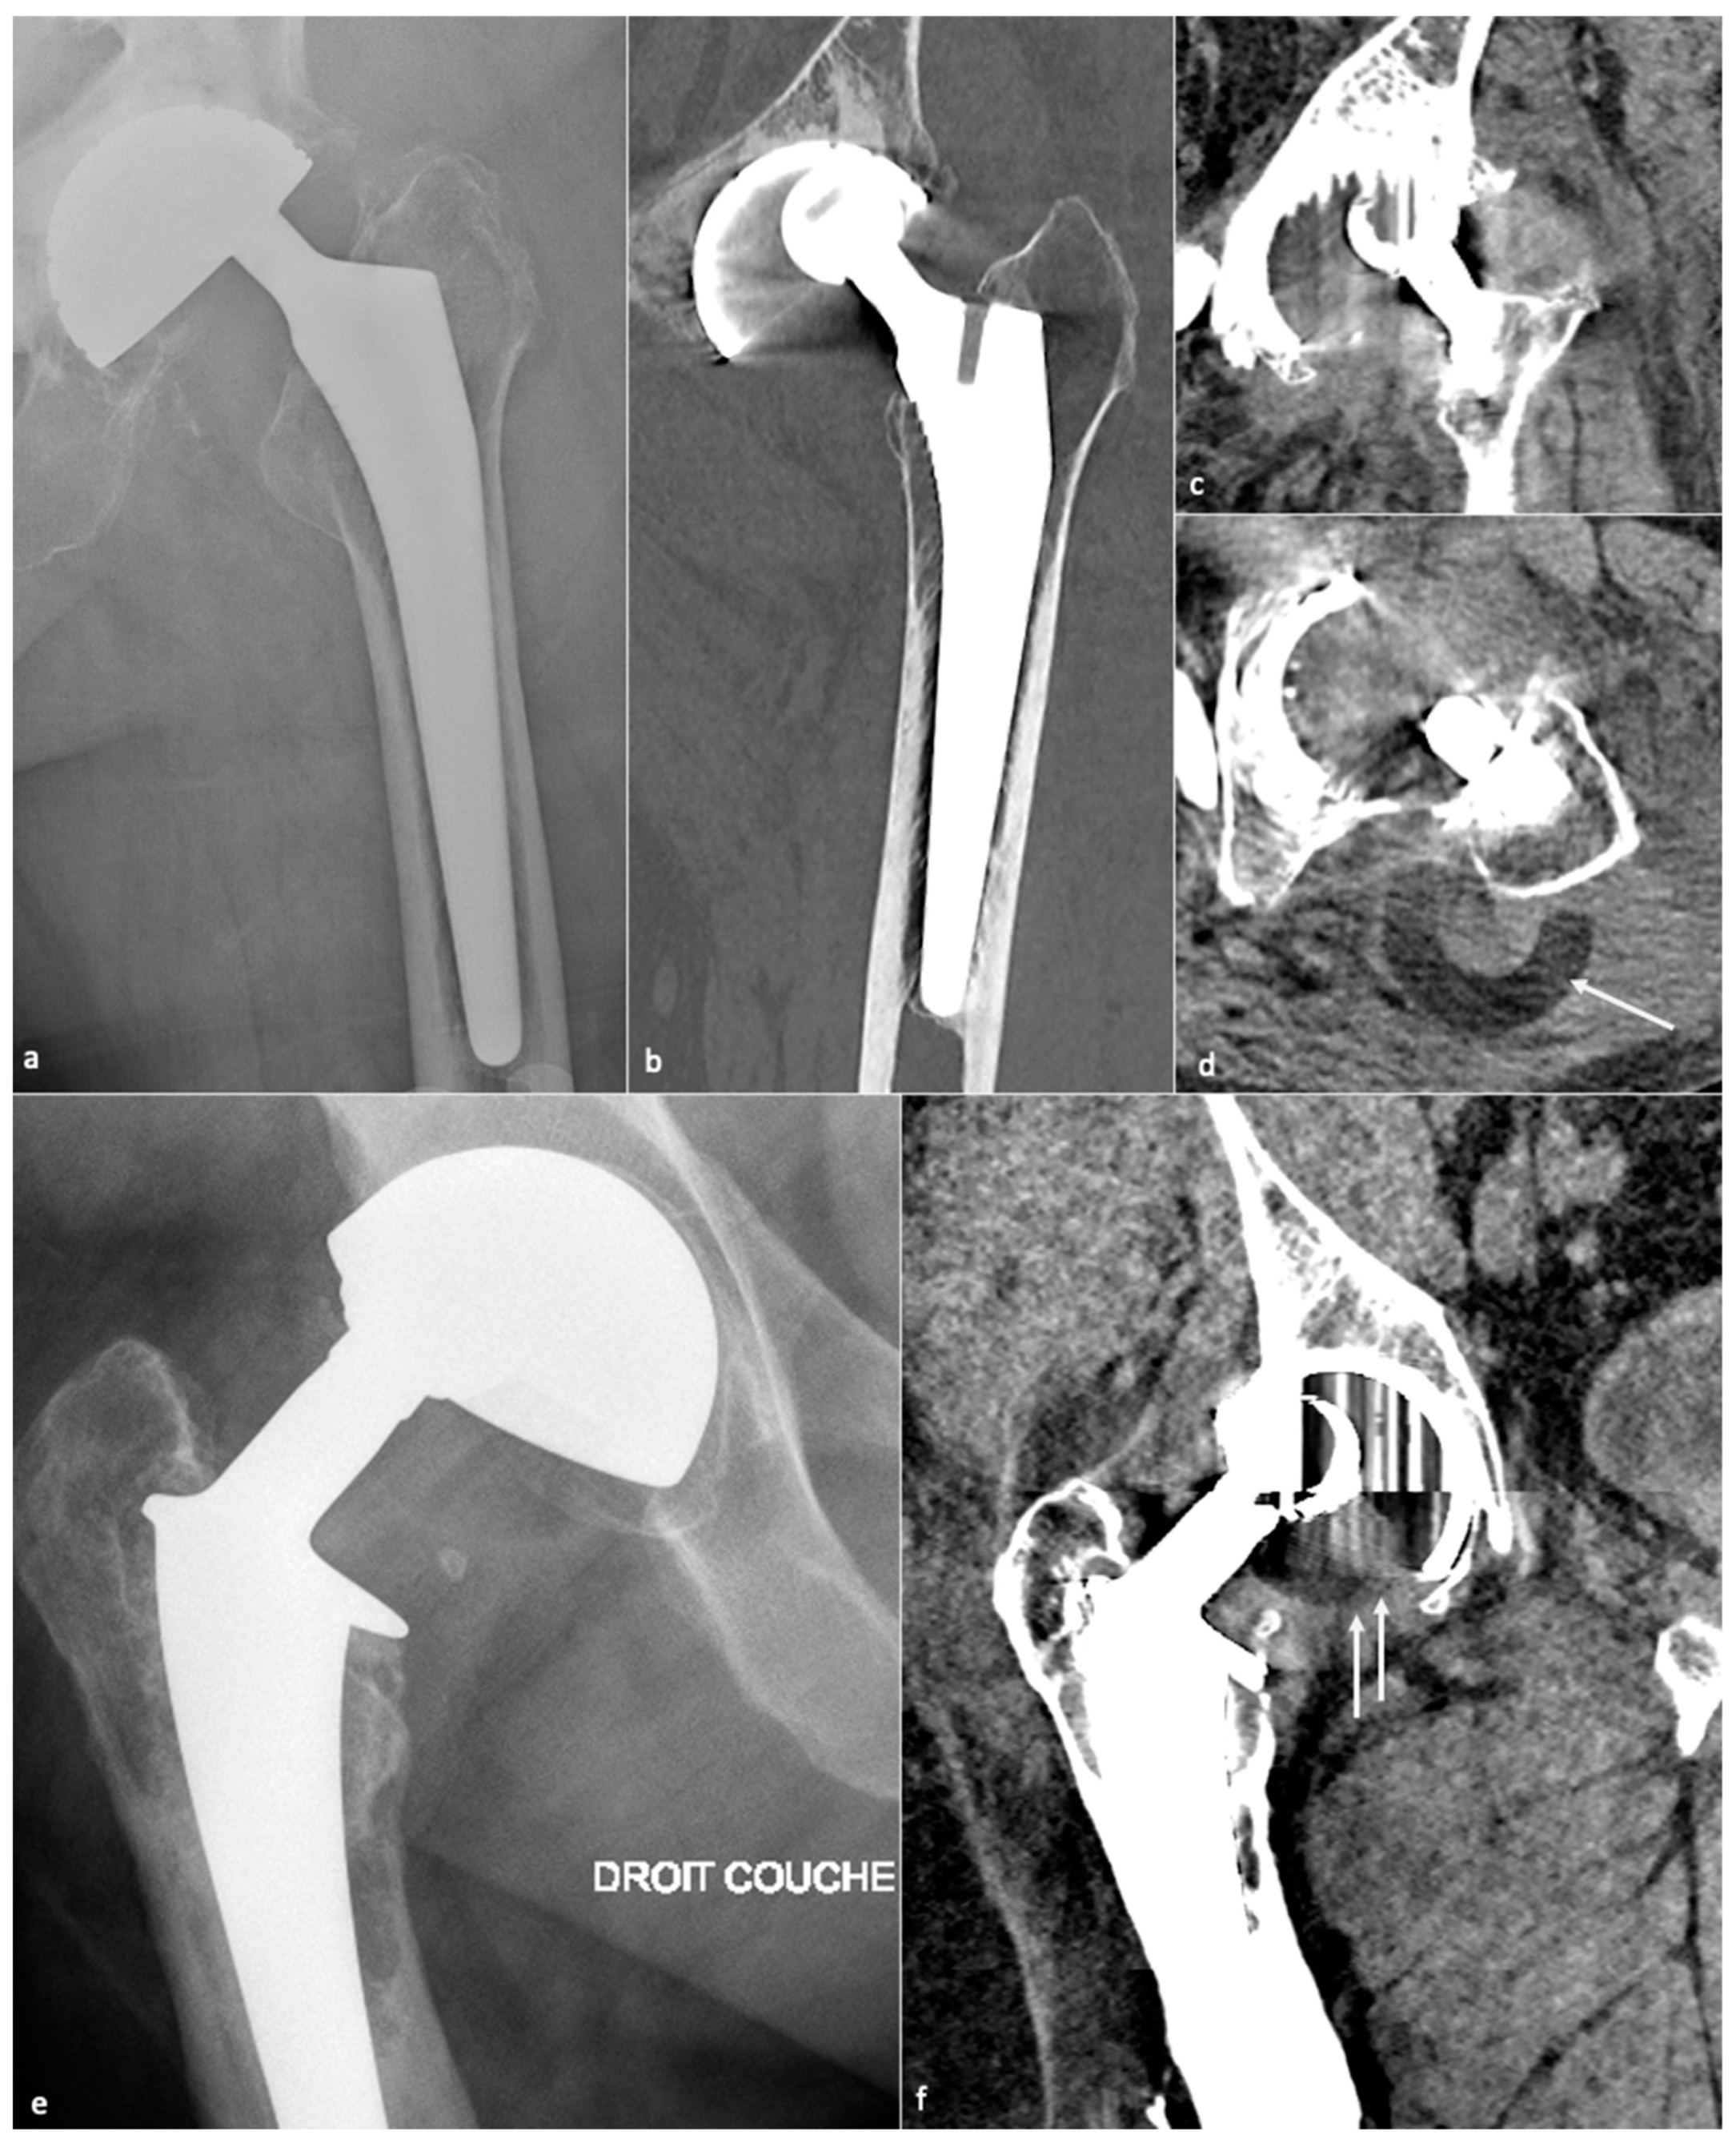

4.1. Dislocation

4.1.1. Background

4.1.2. Imaging

4.1.3. Imaging Perspectives